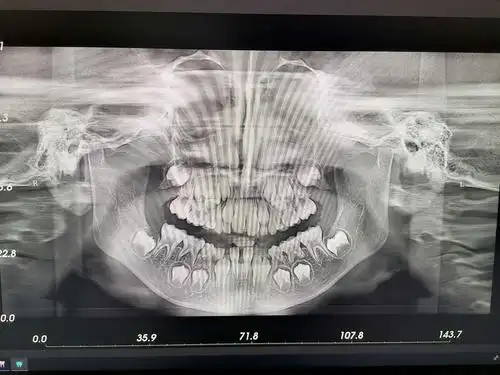

四川大学华西医院龙泉医院超大视野口腔ct投入使用

ct检查,全景,人的嘴,x光,口腔卫生